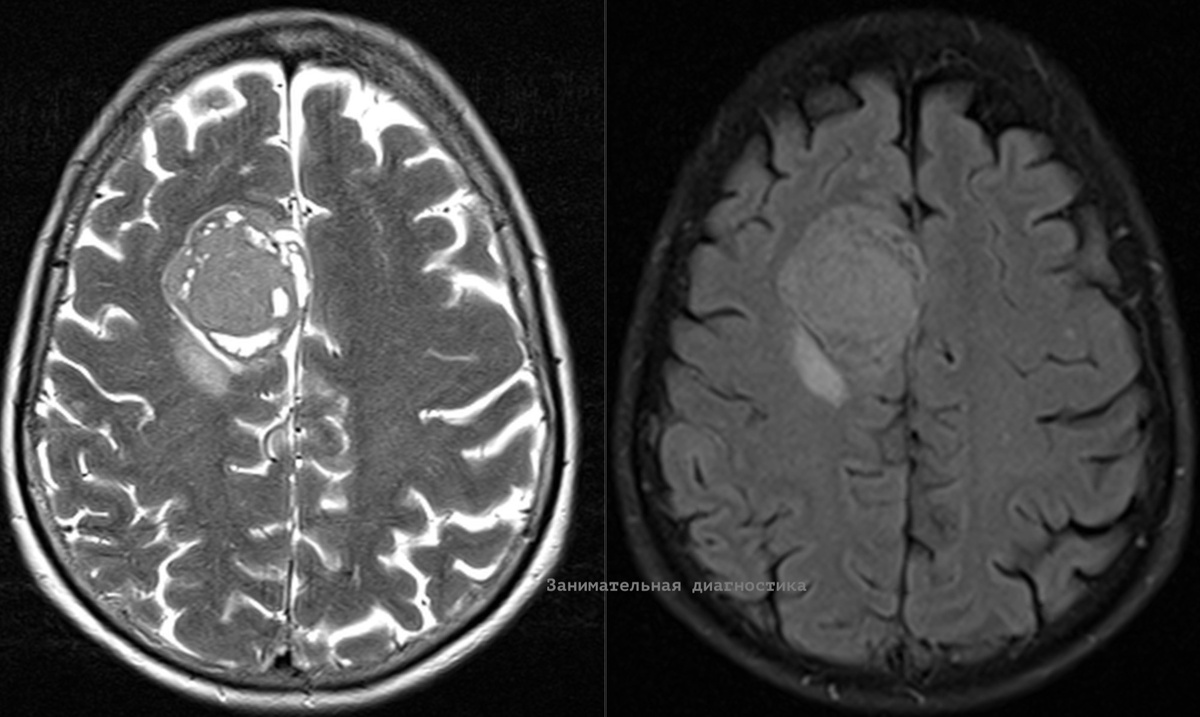

К нам на МРТ обратилась женщина 70 лет у которой ранее обнаружили опухоль на КТ. В таких случаях МРТ назначается для уточнения структуры опухоли и уточнения некоторых других нюансов (для решения по дальнейшей тактике). Образование достаточно крупное, размером с куриное яйцо, оказывает умеренное объёмное воздействие на мозг (масс-эффект). В таких ситуациях рекомендуется выполнение исследования с в/в контрастом. Это позволяет точнее оценить структуру опухоли и часто даже предположить её гистологический тип, что ранее (до эры МРТ) было нереальной задачей. Накопление контрастного препарата интенсивное. Расположение опухоли (она прилежит к твердой мозговой оболочке) и другие признаки позволяют нам на 99% быть уверенным гистологическом типе опухоли, это - менингиома. Менингиомы — это опухоли, которые развиваются из клеток мозговых оболочек, окружающих головной и спинной мозг. Случай интересен ещё и тем, что этих образований у женщины оказалось сразу четыре (!), в разных локализациях. Одно из

Образование достаточно крупное, размером с куриное яйцо, оказывает умеренное объёмное воздействие на мозг (масс-эффект).

В таких ситуациях рекомендуется выполнение исследования с в/в контрастом. Это позволяет точнее оценить структуру опухоли и часто даже предположить её гистологический тип, что ранее (до эры МРТ) было нереальной задачей.

Накопление контрастного препарата интенсивное. Расположение опухоли (она прилежит к твердой мозговой оболочке) и другие признаки позволяют нам на 99% быть уверенным гистологическом типе опухоли, это - менингиома.

Случай интересен ещё и тем, что этих образований у женщины оказалось сразу четыре (!), в разных локализациях. Одно из них мы увидели только после контрастного усиления, слишком оно было мелким.